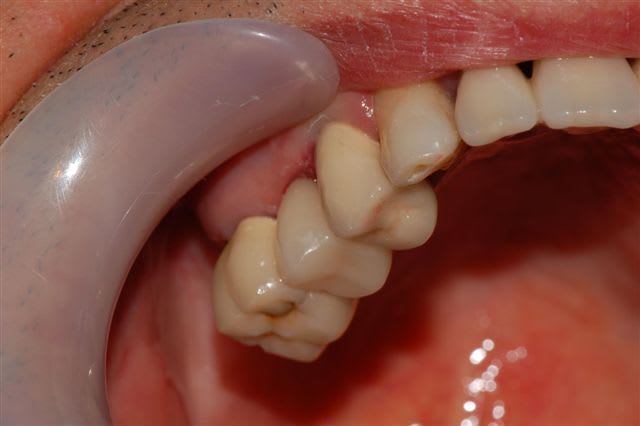

pour ceux qui sont intéressés par le cerec, je posterai également les photos de l'inlay fibré et de la couronne cerec, le tout ayant été réalisé le jour même de l'endo.

Et le patient qui débourse 1000E pour une CR moche sans remboursement, il est content longtemps, tu crois?

Et pour info, la 15 ressemble à la 12 et c'est 14 et 16 qui sont moches!!

le reste, bof, les couronnes 14 et 16 sont moches, et il manque un implant pour la 17...

Après, vu qu'il y a déjà eu des "bof" et "bof bof..", je dirais "mouais..", du travail de cerec quoi, une dent avec une teinte homogène et une anatomie grossière, faut pas être difficile...